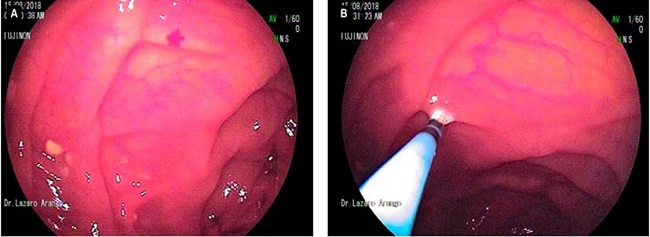

En consecuencia, se decidió realizar una videocápsula endoscópica, cuyo reporte describió la presencia de múltiples lesiones amarillentas, unas planas y otras elevadas, desde el yeyuno alto y 3 en el íleon. De igual forma, se encontró una lesión en el yeyuno medio como posible causa del sangrado, además de algunas angiodisplasias. Estos hallazgos fueron compatibles con una lipomatosis intestinal y malformaciones vasculares.

Se condujo al paciente a una enteroscopia de doble balón que mostró las lesiones descritas por la cápsula (Figura 3). Además, se realizó una terapia con argón plasma para el manejo de la lesión lipomatosa ulcerada y de una angiodisplasia. El paciente evolucionó satisfactoriamente y fue dado de alta.